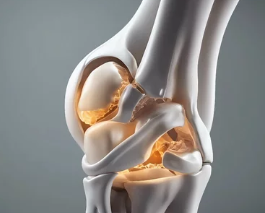

**퇴행성 관절염(Osteoarthritis)**은 나이가 들면서 관절의 연골이 닳아 없어지고, 관절을 이루는 뼈와 인대에 변화가 생겨 통증과 운동 제한이 나타나는 질환입니다. 흔히 ‘나이 들어 생기는 관절병’이라고도 불리며, 무릎, 손가락, 고관절, 척추 등 하중을 받는 관절에 주로 발생합니다. 이번 글에서는 퇴행성 관절염의 대표적인 증상, 초기·중기·말기별 변화, 감별 질환, 진단 및 관리법까지 자세히 정리합니다.

3. 발생 부위별 증상 차이

부위 증상

| 무릎 | 통증, 부종, O자형 다리 변형, 걷기 어려움 |

| 손가락 | 마디가 굵어지고, 통증 + 관절 돌출(헤버든 결절) |

| 고관절(엉덩이 관절) | 사타구니 통증, 다리 들기 어려움, 다리 길이 차이 |

| 척추 | 허리 통증, 신경 눌림에 따른 다리 저림 가능 |

| 발목/발가락 | 통증으로 보행 불편, 신발 신기 어려움 |